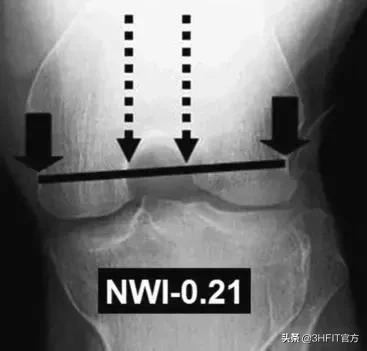

Adam解释道:静态测量在预测前交叉韧带ACL受伤风险上没有那么有用——除了股骨切迹宽度指数。

无论是男性还是女性,股骨切迹宽度越窄,前交叉韧带ACL受伤的风险越高。单腿深蹲或者单腿下台阶的动态膝关节外翻模式,对侧骨盆下沉以及股骨的内旋已经被证实会造成个体膝关节受伤风险上升。